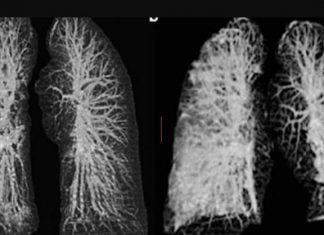

Pamjet shqetësuese, çfarë u bën mushkërive koronavirusi

Disa pamje shqetësuese të publikuara së fundmi tregojnë se çfarë mund t’u shkaktojë koronavirusi mushkërive.

Pamjet e publikuara tregojnë efektin e Covid-19 tek mushkëritë e dy banorëve të Ëuhan-i, që ndodheshin e pushime në Itali....